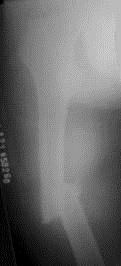

病历摘要: 患者×××,男性,34岁,车祸致伤右大腿后肿胀、疼痛、畸形,活动受限2小时。查体:右大腿肿胀,成角畸形,骨连续性中断,右足背动脉搏动存在,右足...

问题 病历摘要: 患者×××,男性,34岁,车祸致伤右大腿后肿胀、疼痛、畸形,活动受限2小时。查体:右大腿肿胀,成角畸形,骨连续性中断,右足背动脉搏动存在,右足伸屈功能正常。 该患者的治疗首选的是:

选项 A、切开复位、加压钢板内固定 B、闭合穿钉交锁髓内钉内固定 C、股骨髁上牵引 D、皮肤牵引 E、胫骨结节牵引

答案 B

解析 B